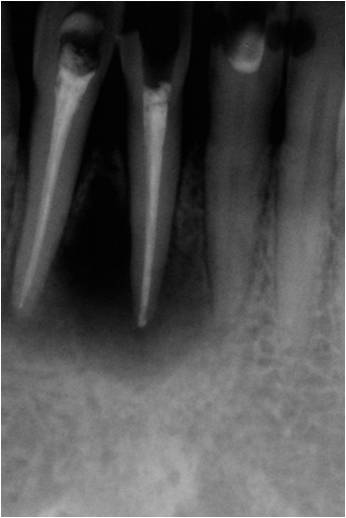

L'endodonzia si occupa della cura dei canali radicolari, cioè quando una carie ha raggiunto la polpa del dente

e l'ha infettato con il relativo mal di denti o gonfiore che ne consegue, l'odontoiatra ha il compito di

devitalizzare il dente, ossia sostituire alla polpa infetta il materiale da otturazione canalare.

Per far ciò è necessario sagomare l'interno del canale del dente e questo viene fatto con gli strumenti Ni-Ti

ciò al nichel-titanio che, essendo flessibili, garantiscono l'accesso anche alle zone più difficili.